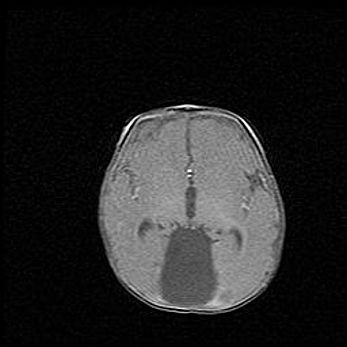

Множественные кисты обоих полушарий головного мозга, наибольшая из них в правой затылочной области. Ассиметричная атрофическая гидроцефалия.

Возраст: 7 месяцев

Вес: 5660 г

Пол: мужской

Окружность головы: 41,5 см

Срок гестации: 28-29 недель

Кисты головного мозга развиваются в результате многоочаговых некрозов вещества мозга и возникают вследствие перенесенной перинатальной инфекции, менингитов, энцефалитов, асфиксии, родовой травмы, расстройств мозгового кровообращения различного генеза. Образованию кист в веществе головного мозга плодов и новорожденных способствуют такие факторы, как высокое содержание в нем воды, недостаточная (или отсутствие) миелинизация и слабая астроглиальная реакция на повреждение.

Кисты могут сочетаться с гидроцефалией и другими поражениями головного мозга.